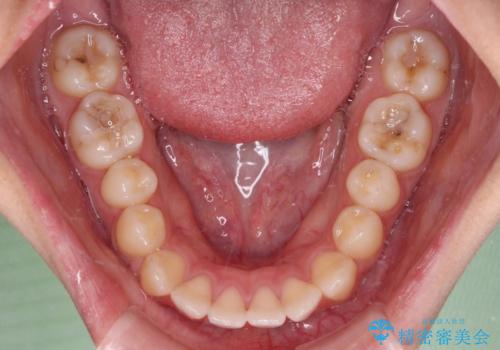

舌のトレーニングをしっかりと行ってくださり、予定通りの期間で理想的な仕上がりを達成することができました。

- 口元の突出感と上下前歯のズレを気にして来院された患者様です。

舌の突出癖により上下の前歯は非接触となっている状態でした。

突出感改善のため、上下左右の第一小臼歯4本を抜歯し、ワイヤー装置にて矯正治療を行うこととしました。